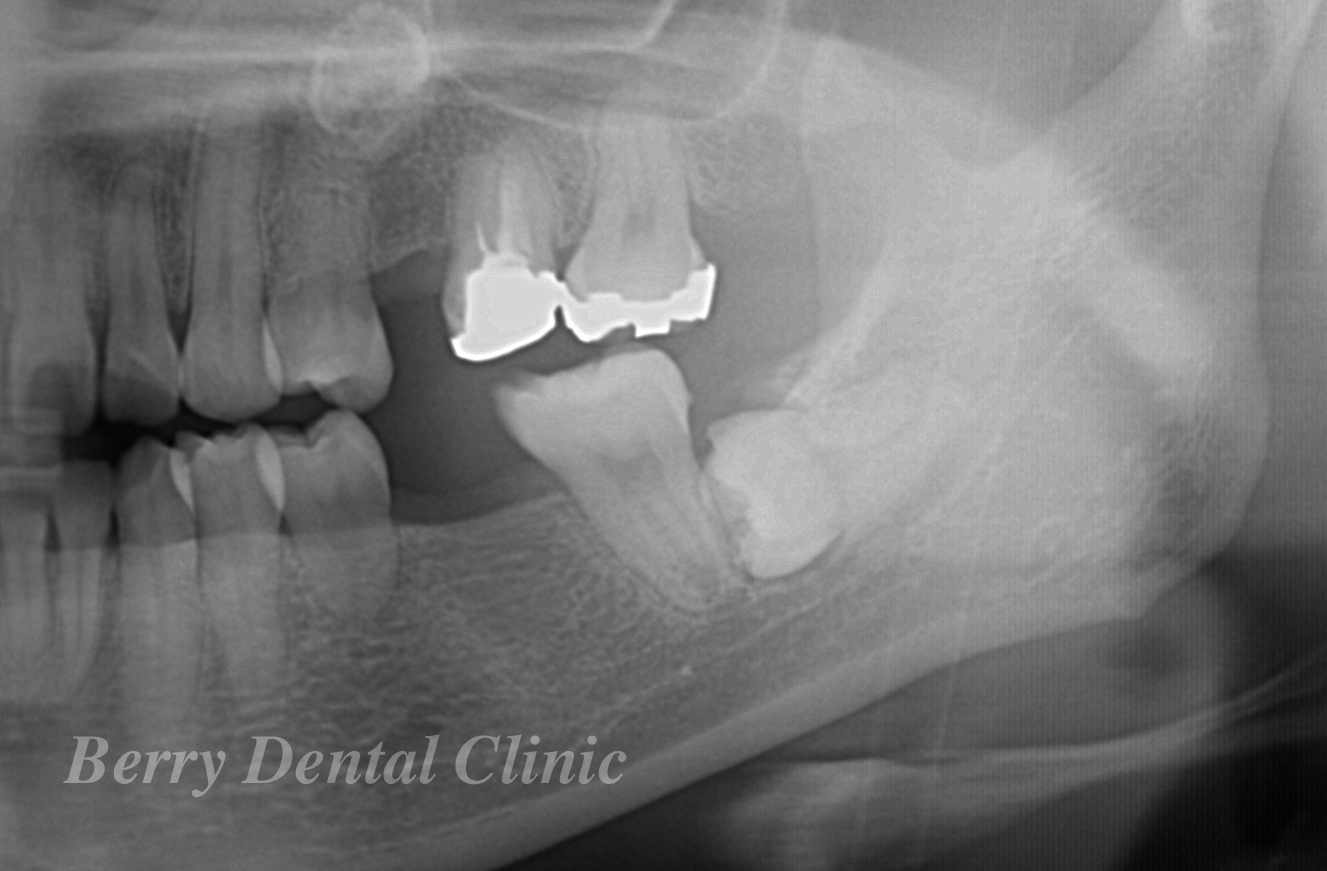

無料相談ということで実際にレントゲンなどのお口の詳しい状態を確認はできませんが、様々な想定をした上でご説明させていただきました。

まずはレントゲン等の大事になお口の情報を得る為の検査をさせていただく事になりました。